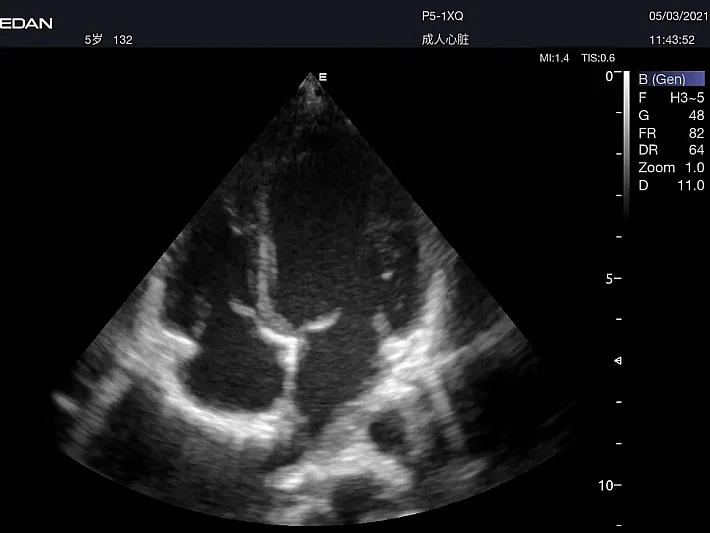

Медицинское оборудование и сервисное обслуживание